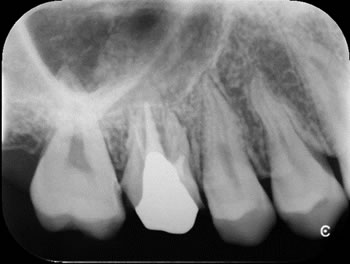

根管治療を成功させるだけでなく、その後の歯の寿命を左右するのが被せ物の質です。当院では、保険適用外となりますが、接着性に優れたセラミック製の被せ物を推奨しています。

セラミックは見た目の美しさだけでなく、細菌が付着しにくく、歯との接着性が高いため、根管への再感染リスクを最小限に抑えられます。

精密根管治療では1回の治療時間を長めにとり(最低60分以上)、治療回数は症例によりますが、2から3回で終了します。根の病気が治らないときは、外科的歯内療法という処置をおこないます。